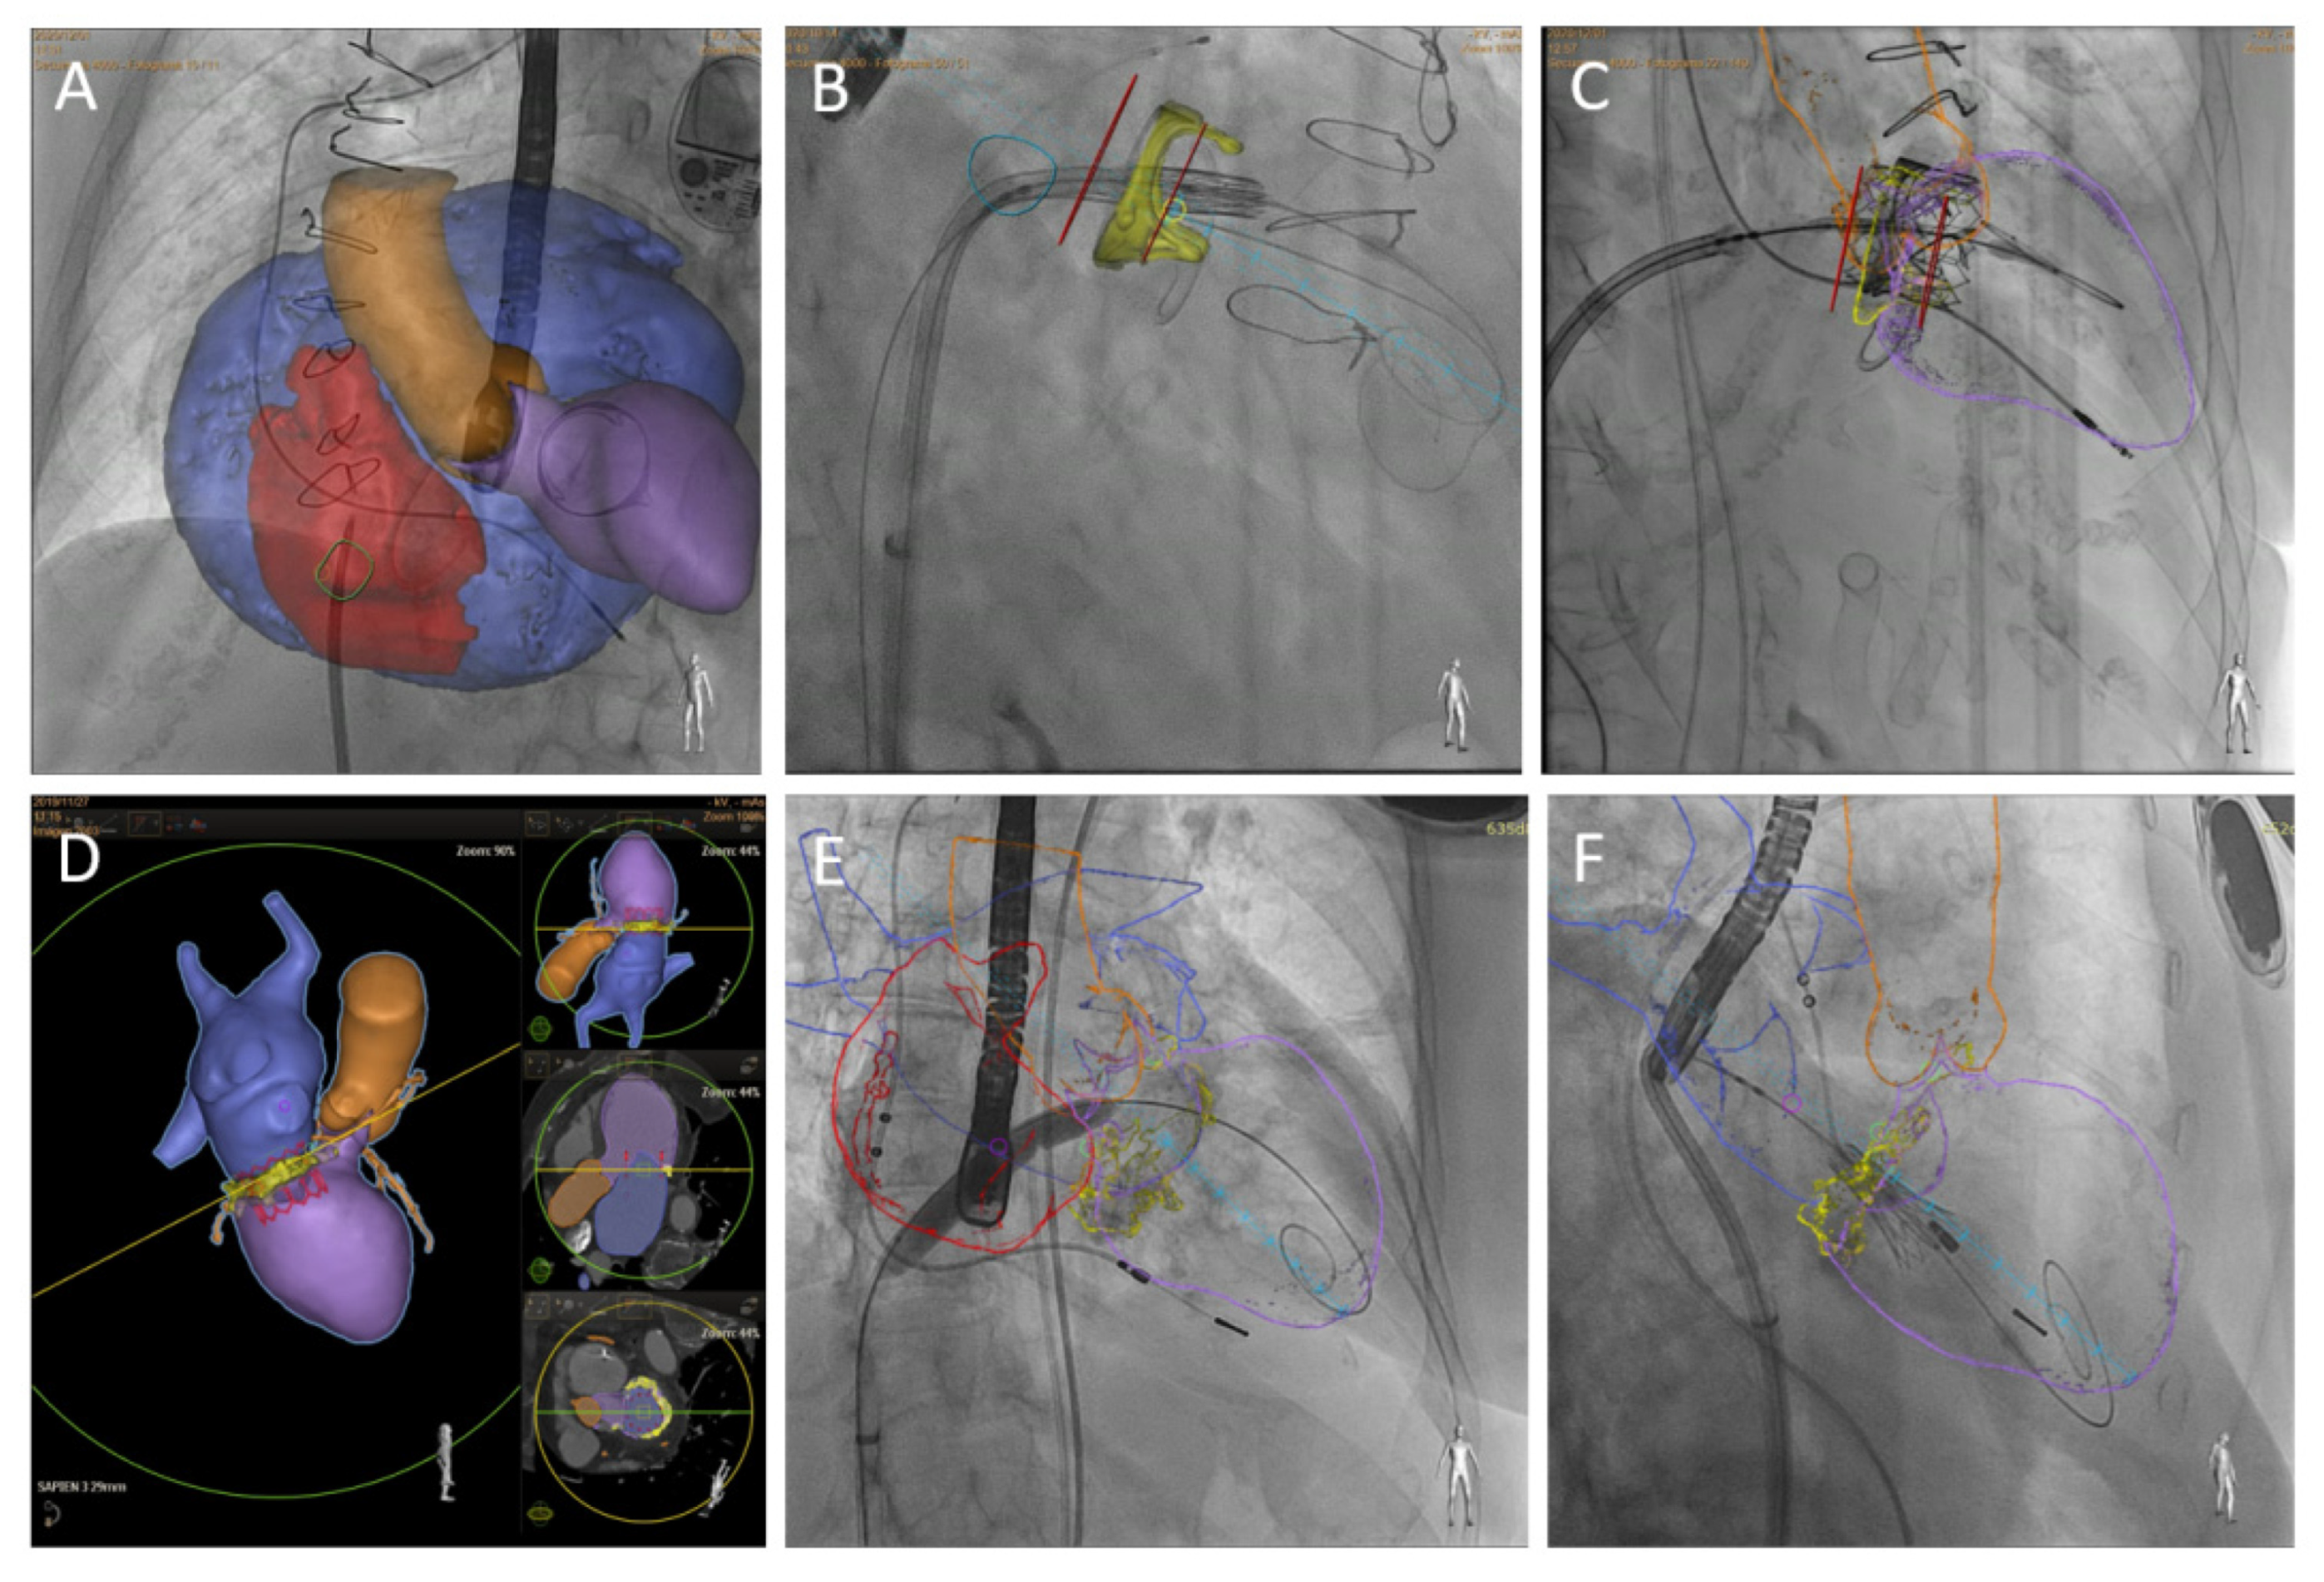

4.3. Fusion Imaging

- Pascual, I.; Pozzoli, A.; Taramasso, M.; Maisano, F.; Ho, E.C. Fusion imaging for transcatheter mitral and tricuspid interventions. Ann. Transl. Med. 2020, 8, 965. [Google Scholar] [CrossRef]

- Barreiro-Perez, M.; Estévez-Loureiro, R.; Puga, L.; Caneiro-Queija, B.; Baz, J.A.; Iñiguez-Romo, A. Real-Time Echocardiography-Fluoroscopy Fusion Imaging With Automated 3D Heart Segmentation During Transcatheter Structural Heart Interventions. JACC Cardiovasc. Interv. 2022, 15, e155–e158. [Google Scholar] [CrossRef]

- Faletra, F.F.; Pozzoli, A.; Agricola, E.; Guidotti, A.; Biasco, L.; Leo, L.A.; Taramasso, M.; Pasotti, E.; Kuwata, S.; Moccetti, M.; et al. Echocardiographic-fluoroscopic fusion imaging for transcatheter mitral valve repair guidance. Eur. Heart J.—Cardiovasc. Imaging. 2018, 19, 715–726. [Google Scholar] [CrossRef]

- Wiley, B.M.; Eleid, M.F.; Thaden, J.J. Fusion Imaging for Procedural Guidance. Rev. Esp. Cardiol. Engl. Ed. 2018, 71, 373–381. [Google Scholar] [CrossRef]

- Nobre, C.; Oliveira-Santos, M.; Paiva, L.; Costa, M.; Gonçalves, L. Fusion imaging in interventional cardiology. Rev. Port. Cardiol. Engl. Ed. 2020, 39, 463–473. [Google Scholar] [CrossRef] [PubMed]